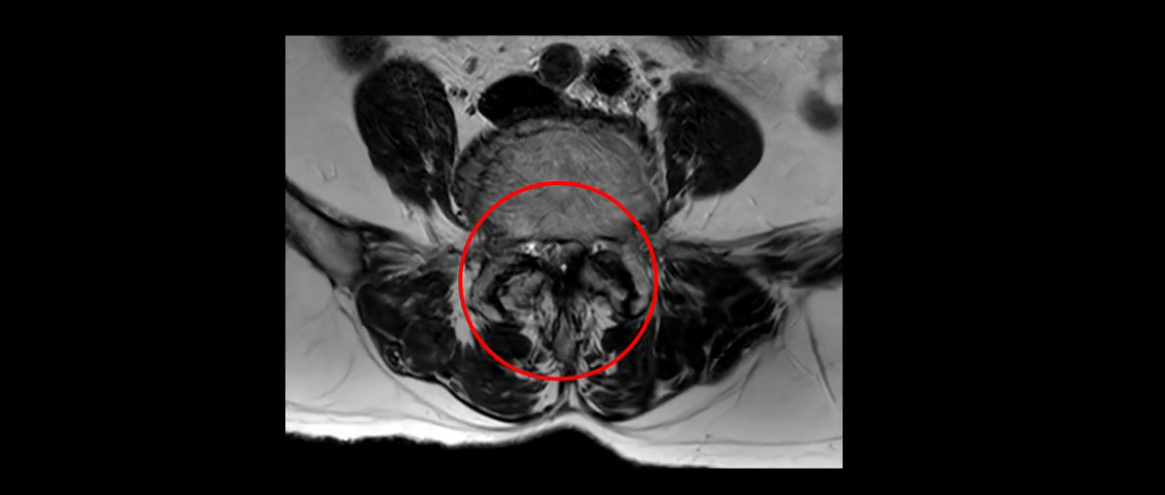

이분 MRI 보시면 허리 3마디의 퇴행이 매우 심합니다.

또 척추관협착도 매우 심합니다.

척추관이 심하게 좁아져 있습니다.

이렇게 여러 마디가 안 좋고 뼈도 밀려 나가 있으니까 나사박는 수술해야 하는데, 대학병원에서도 수술을 한 번에 못 하고 두 번에 나눠서 해야 한다고 들으셨습니다. 왼쪽으로 신경가지가 빠져나가는 추간공도 많이 좁아져 있습니다.

이렇게 신경 구멍들이 좁아져 있고 신경이 눌리니까 엉덩이와 다리가 너무 저리고 아파서 아예 일어서질 못하니까 휠체어를 타고 병원에 내원하셨는데요. 그럼 어떻게 이분처럼 신경이 눌려있는 환자분들을 수술 없이 치료해서 잘 걷게 만들고 엉덩이와 다리가 저리고 아픈 증상이 사라지게 할까요? 지금부터 설명해 드립니다.